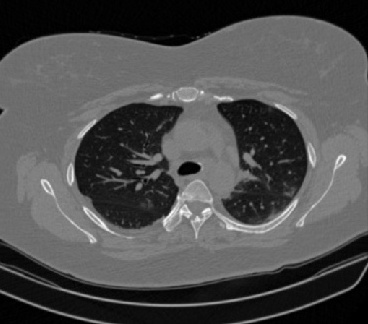

It should be mentioned that for explainability purposes [7, 8, 9], an anchor set was generated for the COV19-CT-DB database [5]. This included 11 anchors, each representing a respective 3-D CT scan obtained through an appropriate clustering procedure. Figure 2 shows a series of slices from a COVID-19 case, whereas Figure 3 shows a series of slices from a non COVID-19 case.